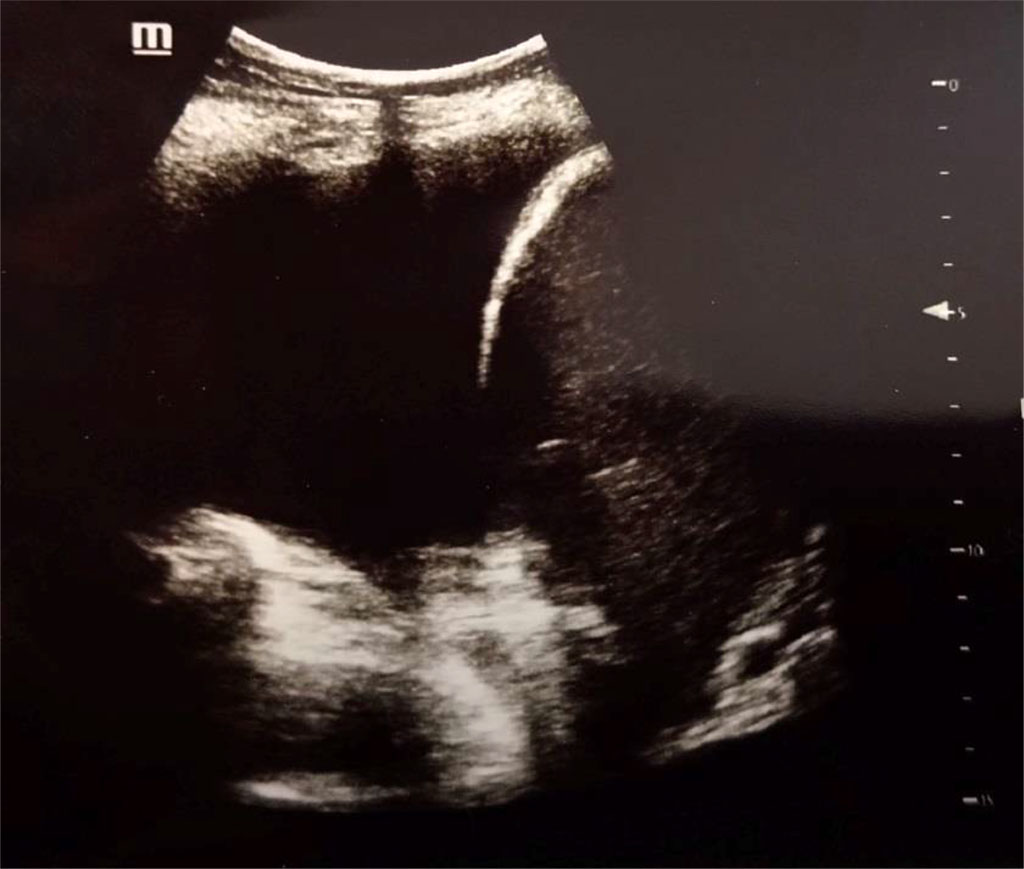

Figure 3. Pleural effusion (anechoic), diaphragm and liver at the right side. Author’s private materials.